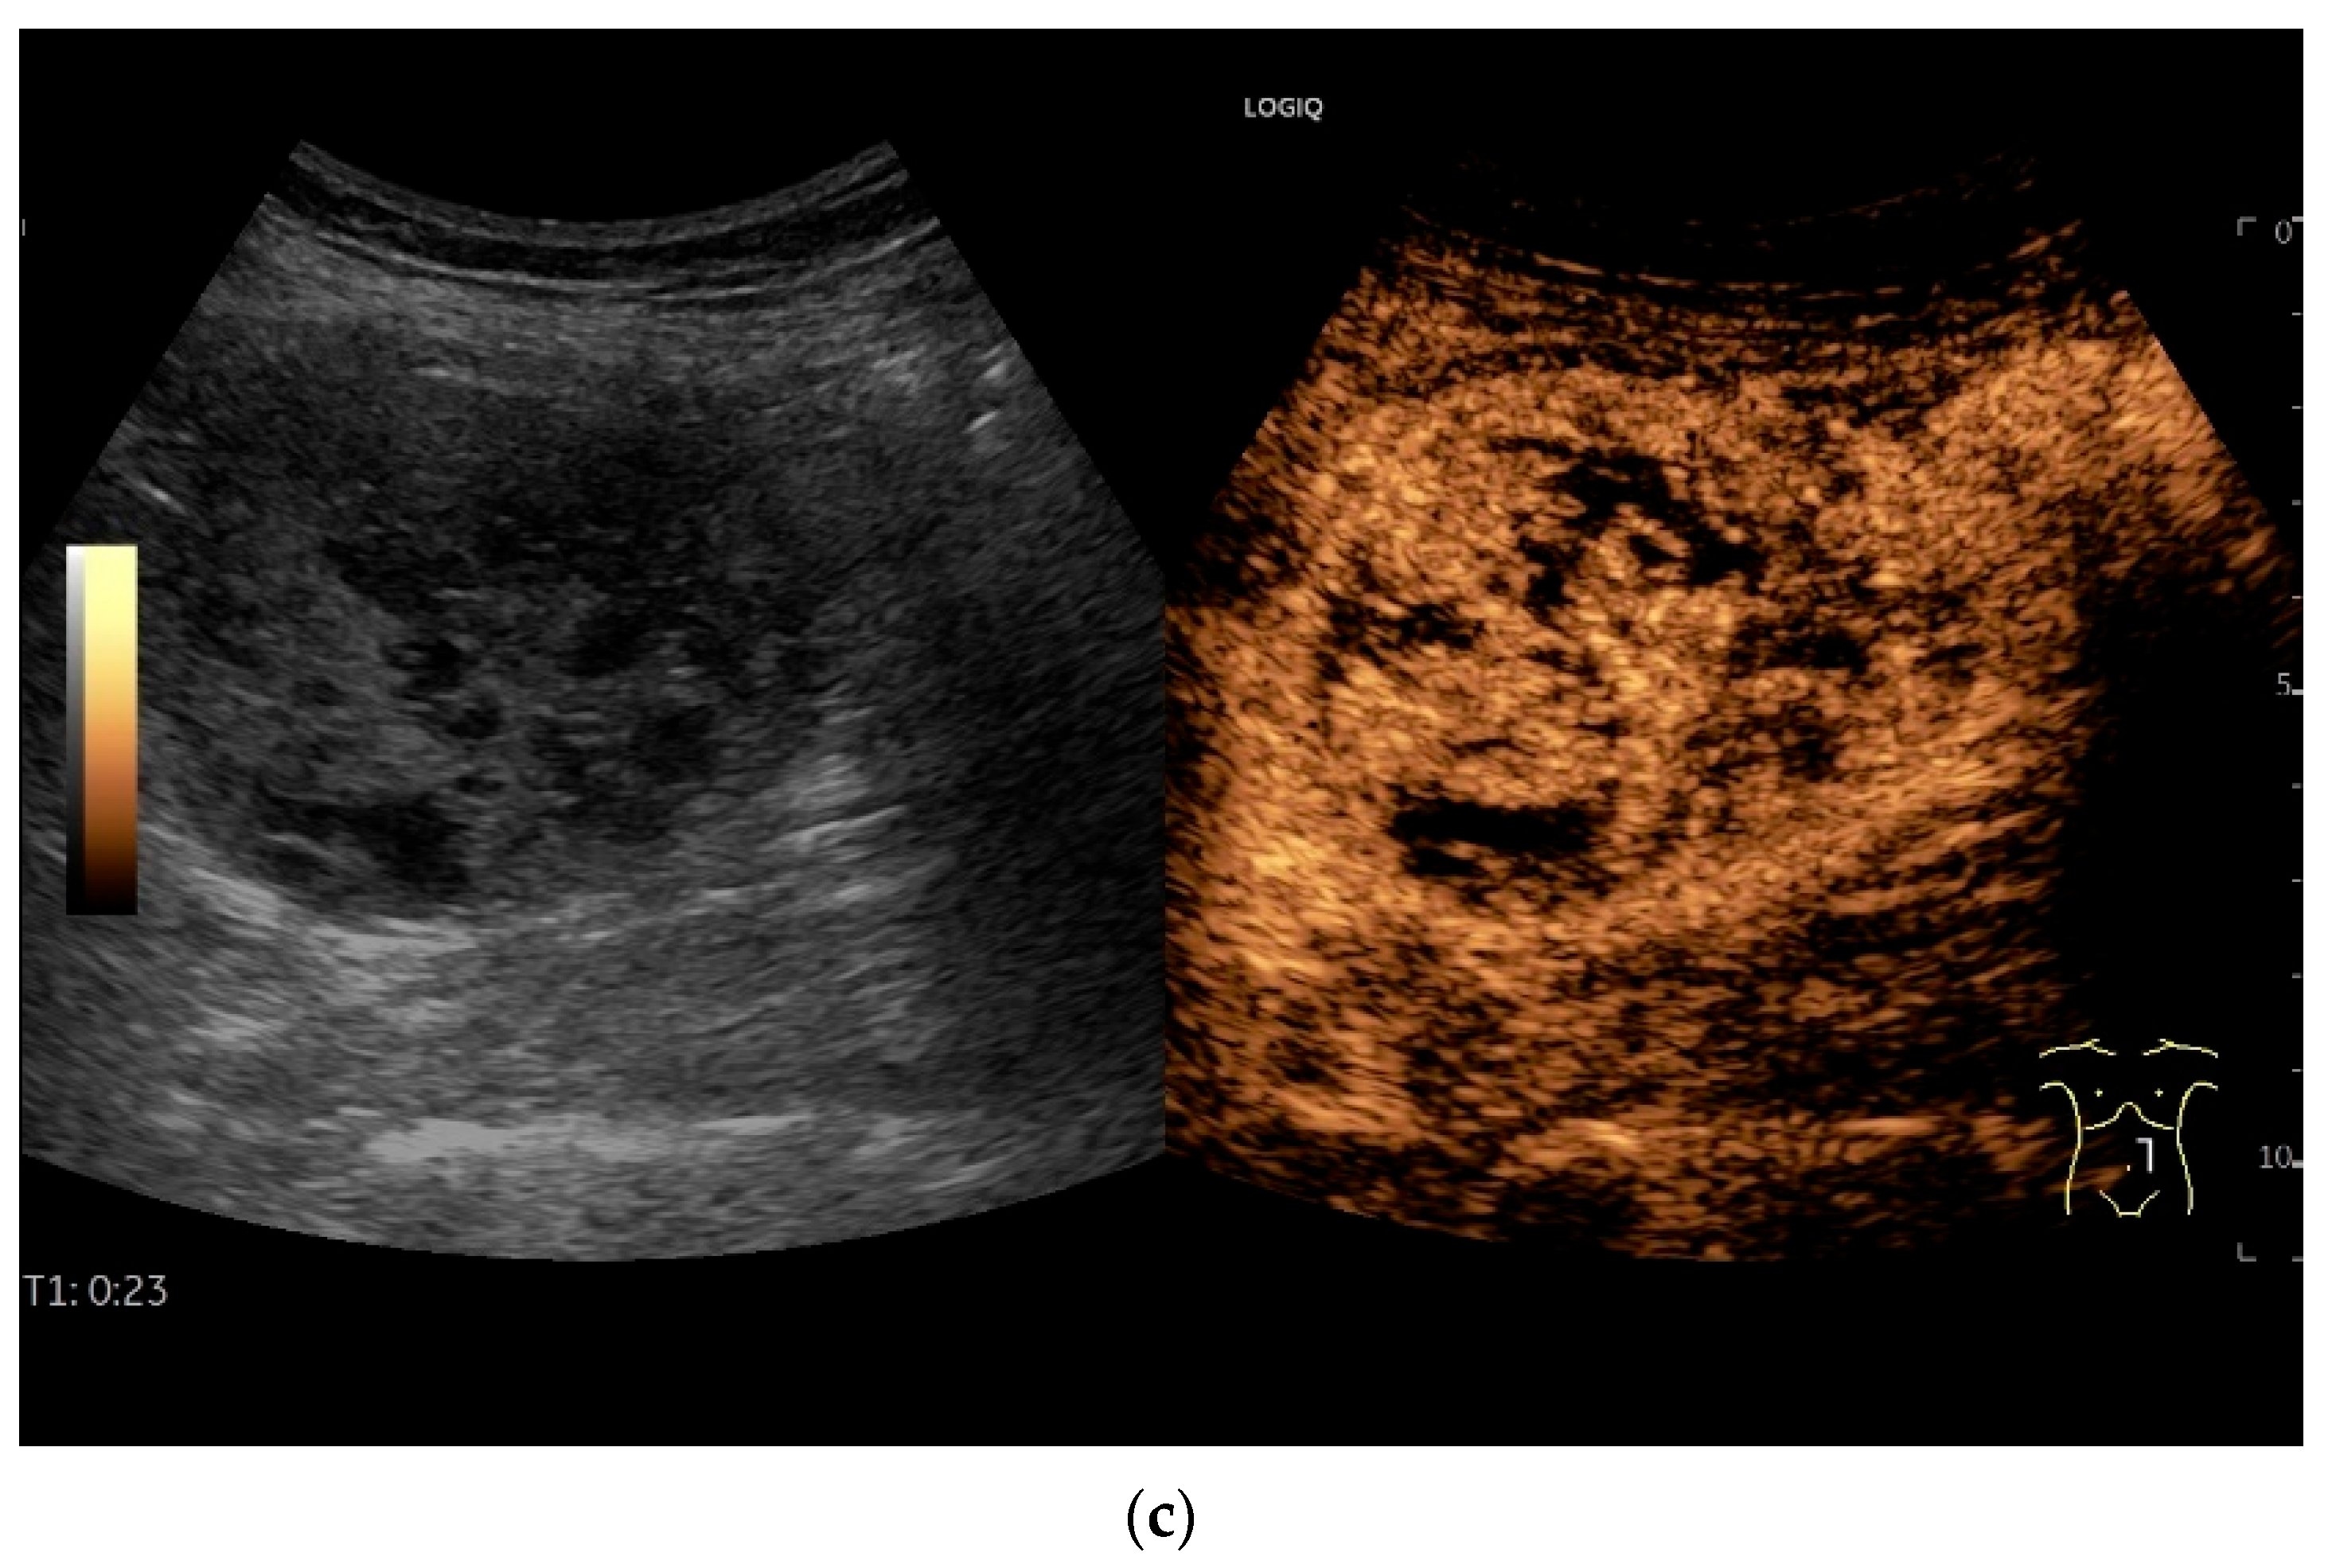

Figure 10.

Diffuse large B-cell lymphoma (DLBCL). In the right mid-lower abdomen, a large, smoothly circumscribed mass is present around the ileum (“pseudo kidney sign” (a)). Using a high-resolution linear transducer, the mass appears smoothly circumscribed and almost anechoic (b). The ileum runs centrally, and the echogenic wall is clearly defined (c). This wall does not merge into the mass. Since the mass is almost anechoic, it is also difficult in different transducer positions to distinguish whether it is a liquid lesion or a solid mass (b,c). CEUS with 2.4 mL SonoVue (9 MHz linear transducer) shows homogeneous arterial enhancement (d), but the intensity decreases with time in the venous phase (e). The ileal wall enhancement centrally within the mass is more intense than that of the tumor (d,e).

In a study of Hasaballah et al. [113] including 21 patients with small intestine lymphoma (90% DBLCL), marked wall thickening (15.6 ± 5.9 mm) with loss of stratification (76%) and high hypoechogenicity were the typical features of the lymphoma manifestations. In 85.7% the lymphoma was unilocular. Further features were dilatation of the intestinal lumen and periintestinal enlarged lymph nodes. US-guided biopsy was performed in 33% of patients and was successful in 100% [113].

Zhang et al. [115] distinguished the mass type, wall thickening type and non-specific signs in 19 intestine lymphomas. The mass type was characterized by solid and cystic-solid hypoechoic lesions with well-defined margins. Among them were pronounced hypoechoic lesions with dorsal enhanced cancellation. On CDI, abundant blood signals were visible in large masses.

The wall thickening type was characterized by thickening of the bowel walls with hypoechoic (including marked hypoechoic) foci and posterior acoustic enhancement. Nonspecific signs included dilatation of the bowel and enlargement of the mesenteric lymph nodes [115].

Cui et al. [116] described four sonographic patterns on B-mode US in 18 patients with small intestine lymphoma. The majority (61%) were DLBCL. The mass type (66.7%) presented as circumferential, marked intestinal wall thickening. The wall was highly hypoechoic with loss of stratification. The central luminal reflex was hyperechoic. The infiltrative type (5.6%) was a segmental thickening of the bowel wall without visible mass formation with a bowel wall thickness of 2.6 cm in a single case. The mesenteric type (22.2%) was characterized by multiple hyperechoic heterogeneous mesenteric masses with or without involvement of the adjacent bowel wall. The lesion sometimes encapsulated mesenteric vessels without stenosis of the vessel lumen. The mixed type (5.6%) showed a combination of two patterns [116].

On CEUS all small intestine lymphomas showed arterial enhancement (hyperenhancement in 17 of 18 cases) followed by venous washout. Tumor necrosis was observed in 61% of cases, which occurred more frequently in aggressive subtypes than in indolent subtypes. There was no correlation between tumor size and necrosis [116].